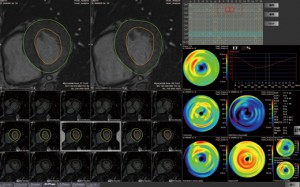

○MR心機能解析2(図2)